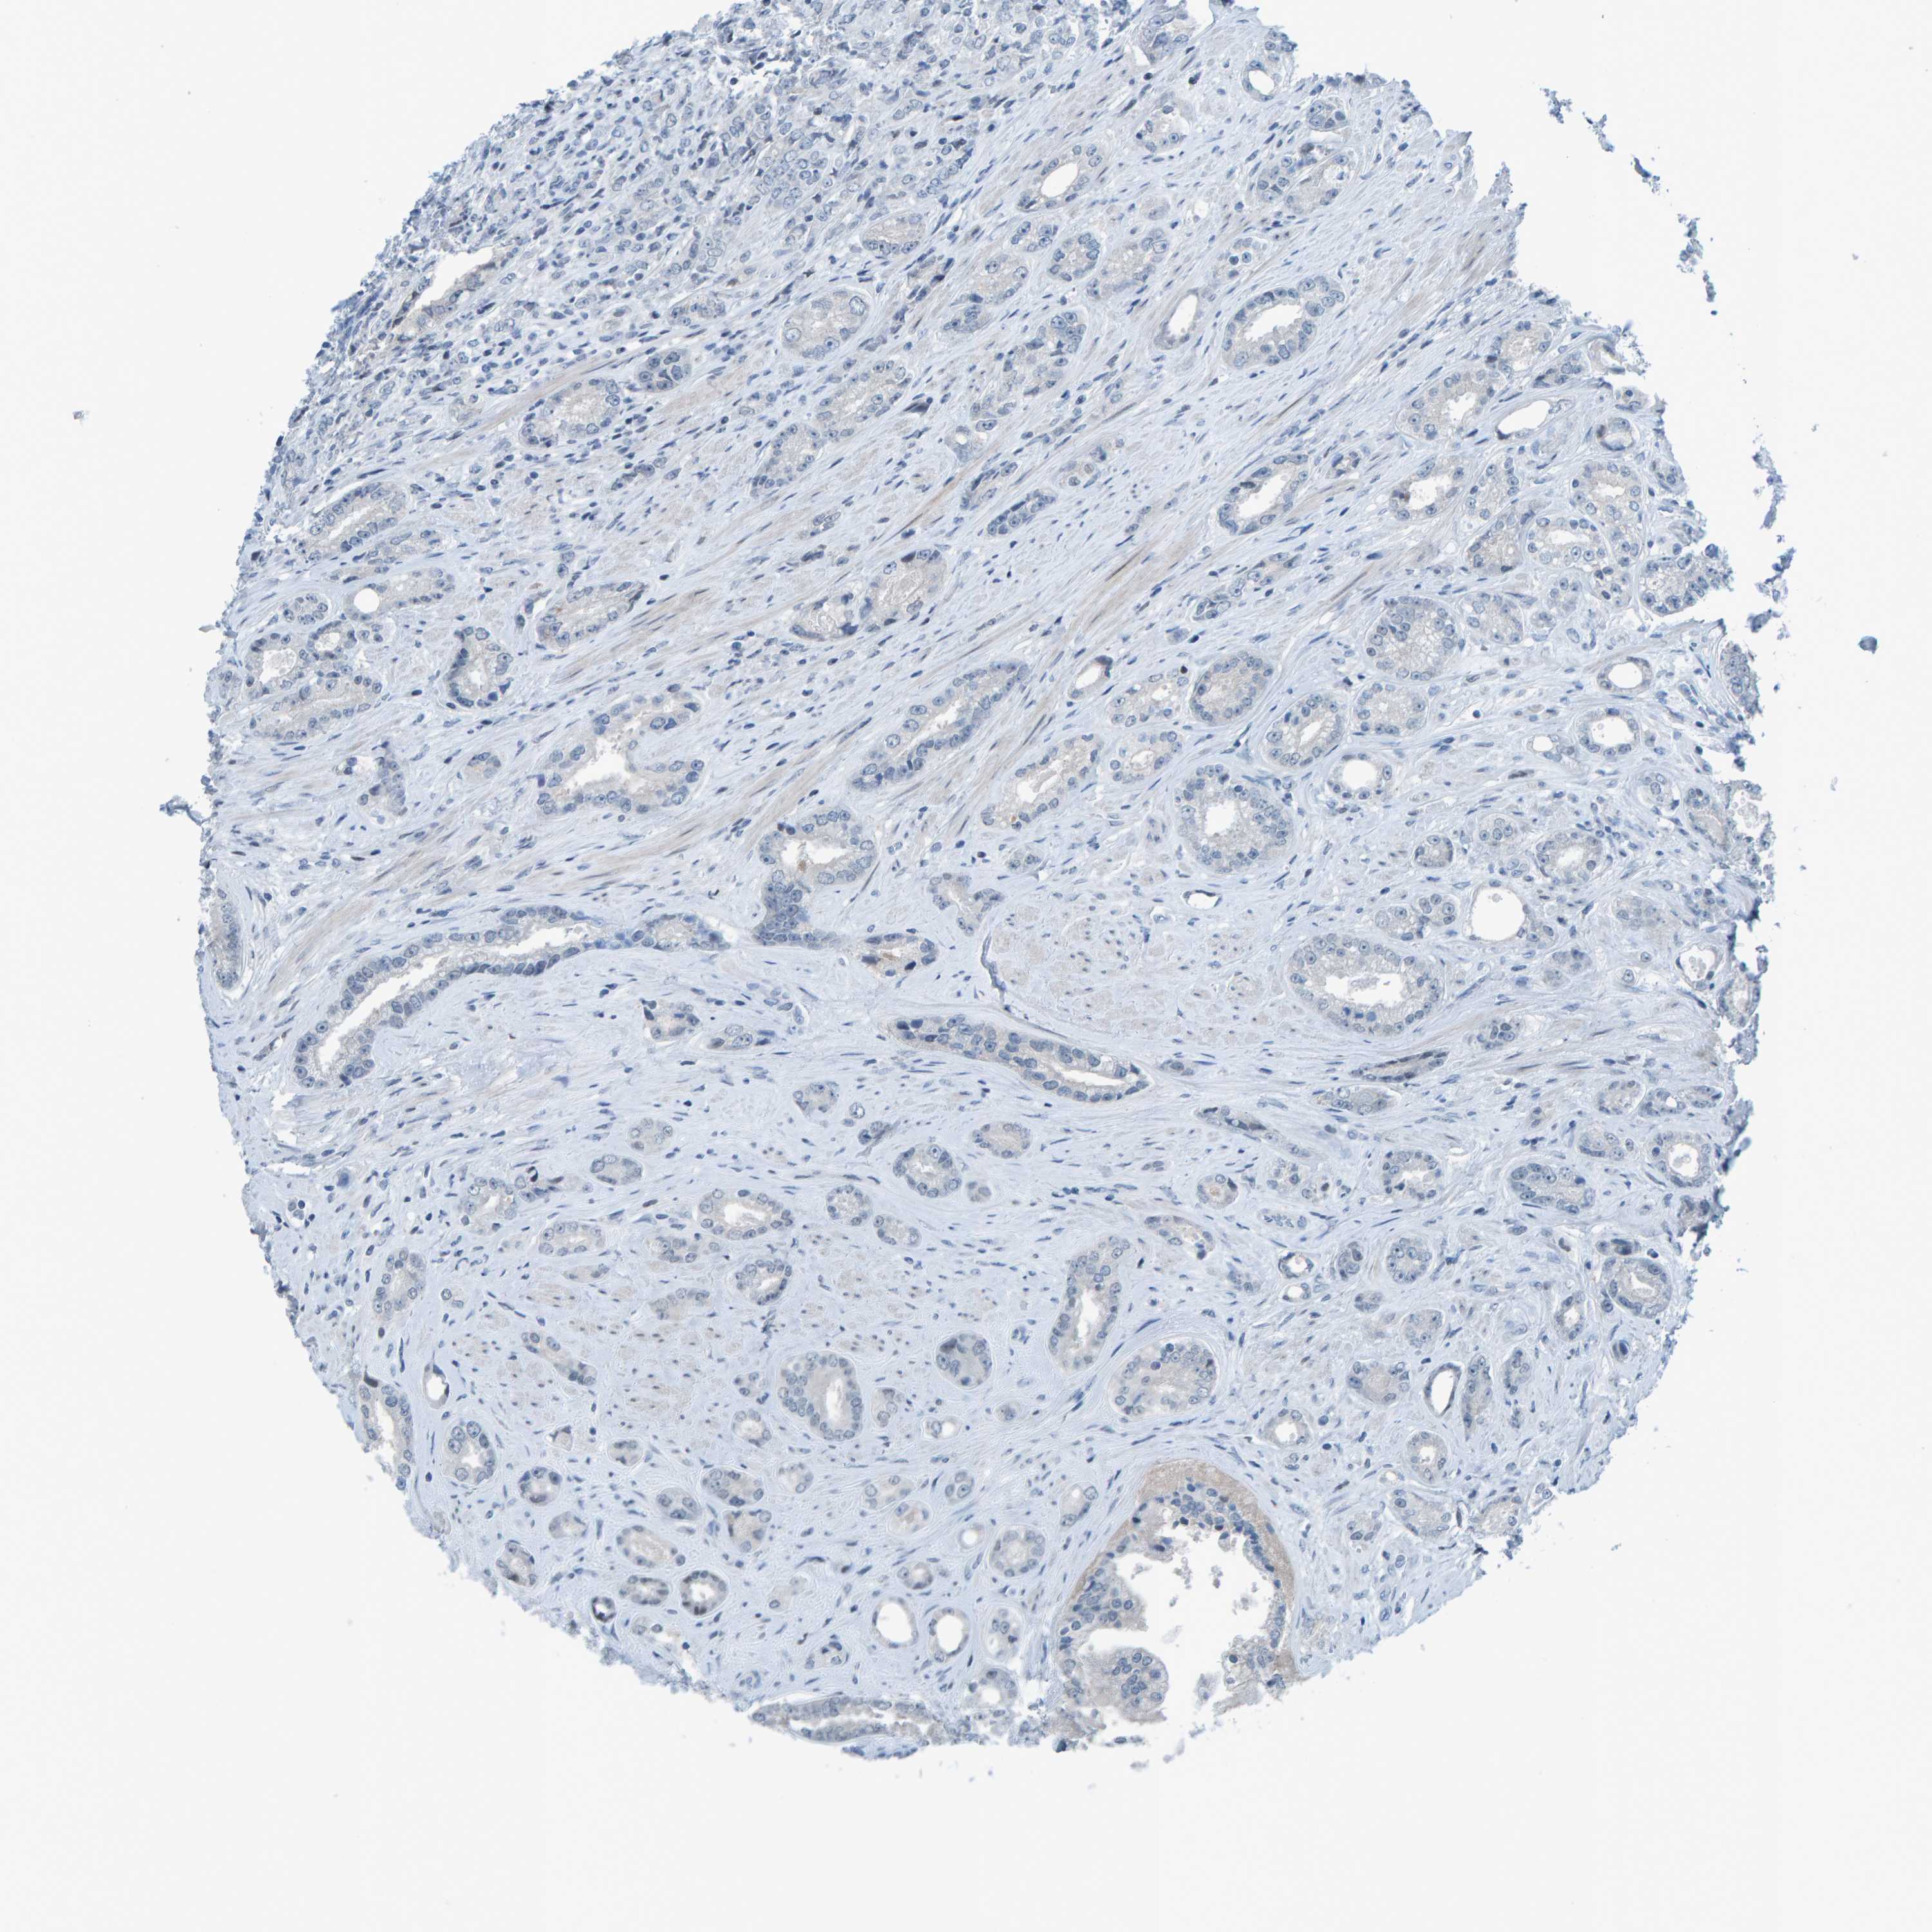

PROSTATE CANCER - Protein expressioni

A mouse-over function shows sample information and annotation data. Click on an image to view it in a full screen mode. Samples can be filtered based on level of antibody staining by selecting one or several of the following categories: high, medium, low and not detected. The assay and annotation is described here.

Antibody stainingi

Antibody staining in the annotated cell types in the current human tissue is reported as not detected, low, medium, or high, based on conventional immunohistochemistry profiling in selected tissues. This score is based on the combination of the staining intensity and fraction of stained cells.

Each image is clickable and will lead to virtual microscopy that enables deeper exploration of all samples and also displays staining intensity scores, fraction scores and subcellular localization as well as patient and tissue information for each sample.